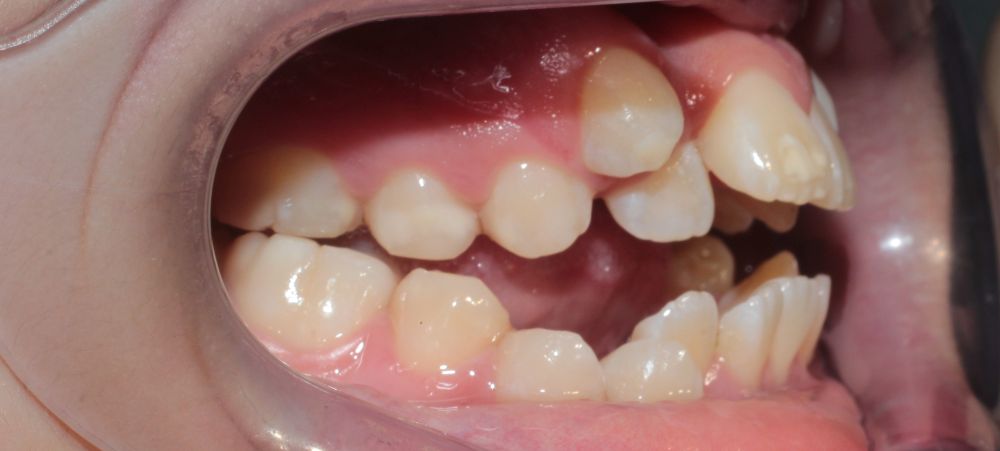

If your child has crowded teeth, snores or has a tired, open-mouthed look, there’s likely more going on than spacing – these are signs of airway restriction.

Narrow V-shaped upper jaw?

Full mouth of baby teeth with no spacing

Airway and jaw issues develop gradually, in ways that seem normal at first. Mouth breathing, crowded teeth, a recessed chin—these signs feel subtle because they happen slowly.

Well developed U-shaped upper arch

Under-developed V-Shaped upper arch